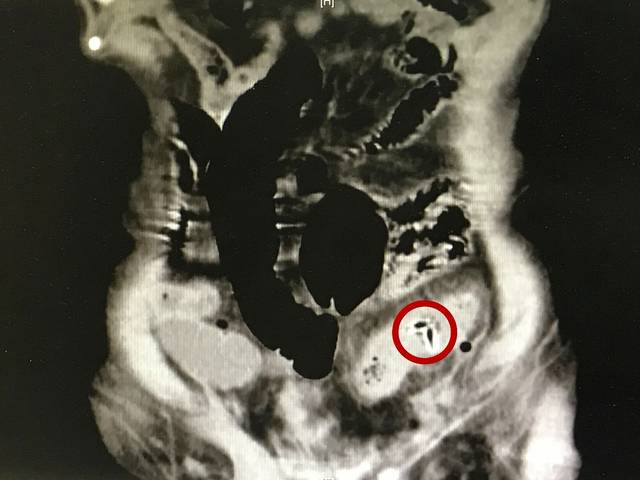

就在不久之前,张鹏接诊了一位92岁的患者。老人日常爱吃枣子,这天突然感到腹痛前来就诊。做腹部CT发现这位老人的乙状结肠和降结肠相连的部位被一个尖锐的异物刺穿,造成感染,伤口附近已经产生炎症和水肿,若进一步发展下去可能会有粪便漏至腹腔,导致严重感染甚至危及生命。在麻醉科、手术室的大力配合下,张鹏医师为老人实施了全麻下的肠切除与造瘘术,切掉被刺破的肠管及周围发炎的部分,并取出了罪魁祸首——枣核。经过ICU及胃肠外科的精心护理,老人已经顺利恢复出院。

图中红圈所示为枣核